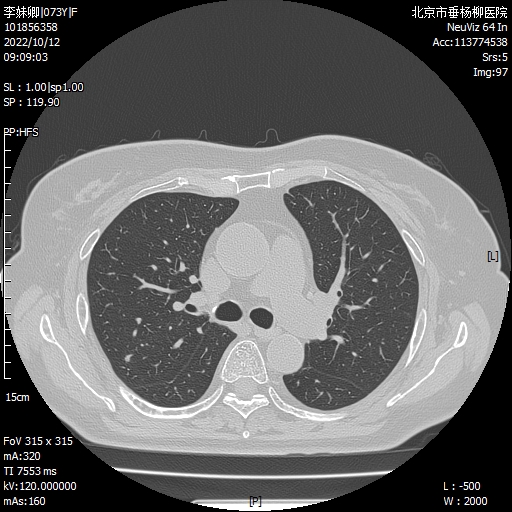

病例概要:患者女性,73岁,主因“发现右肺结节7月。”以“右肺结节,性质待查”入院,胸部CT:右肺可见多发磨玻璃微结节影,边界较清,大者直径约4mm。抗炎治疗无效,恶性不除外,行电视胸腔镜辅助下右肺上叶后段切除术,术中可见脏壁层胸膜光滑,叶裂分化完全,术顺,手术历时2小时,完整切除可疑结节病灶,术后病理回示,分别为:1.不典型腺瘤样增生(AAH);2.良性病变(肺泡上皮轻度反应性增生,伴炭末沉积及淋巴细胞聚集)。术后患者恢复良好,术后2天拔出引流管,4天出院。